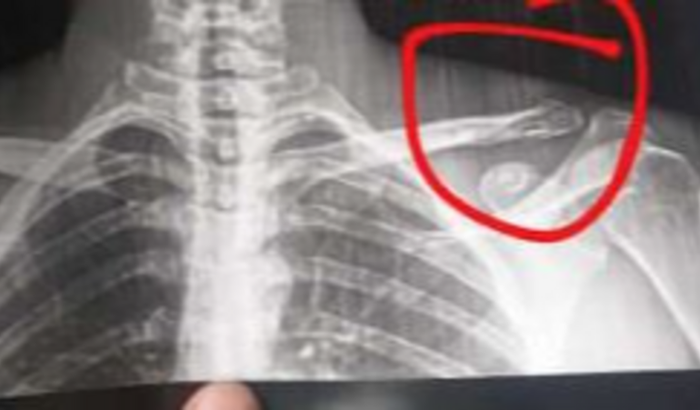

Fala povo lindo! Turobom? Acho que a maioria já sabe que tenho um irmão mais novo, que ele é motoboy (faz entregas pelo iFood) e que essa é a única fonte de renda dele no momento. Ontem, 05/12/2022, uma cidadã abençoada (para não dizer outra coisa) entrou na contramão e ele bateu de frente, na queda ele quebrou a ponta da clavícula e vai ter que ficar de molho por um tempo. Porém as contas não vão esperar ele se recuperar, então eu criei essa vakinha para ajudar ele durante esse período de recuperação, já que ele vai ter que ficar de repouso com o ombro imobilizado. Desde já agradeço de coração a ajuda ♥